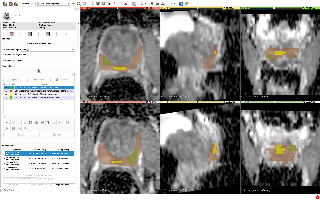

| QIN-PROSTATE-Repeatability | 前列腺癌 | MRI | 15 | dcm | ||